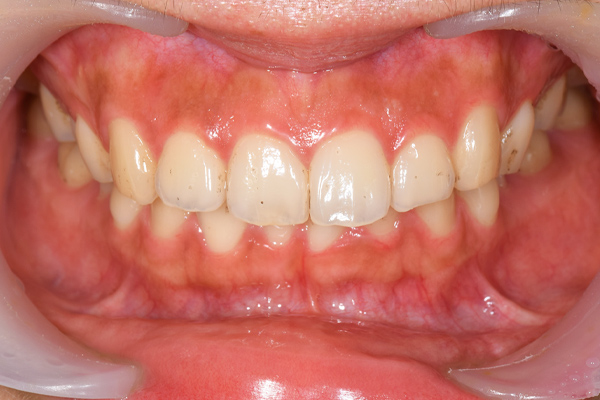

インレー症例

治療前

治療後

治療期間 8回(2ヶ月)

費用 ・セラミックインレー9本

合計:495,000円

治療リスク・副作用 ・詰め物、被せ物をする時は自分の歯を削ることになります

・歯ぎしり・食いしばりが強い方は、セラミックが割れてしまうことがあります。